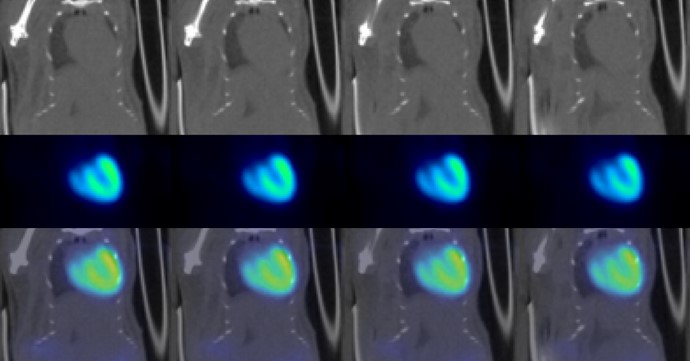

• Gated cardiac imaging

• Patented 2-5 x dose reduction

• Fully automated high precision motorized animal transport system for precise animal positioning and automatic image co-registration and fusion